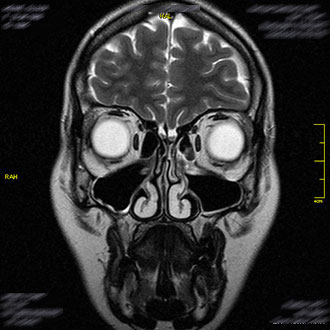

Die MRT der Nasennebenhöhlen wird zur Diagnose von Entzündungen, chronischer Sinusitis oder Karzinomen eingesetzt. Sie zeigt die Schleimhäute und knöchernen Strukturen des Gesichtsschädels detailliert und hilft, die Ursache von Druckgefühlen, Kopfschmerzen oder Nasenatmungsproblemen abzuklären.